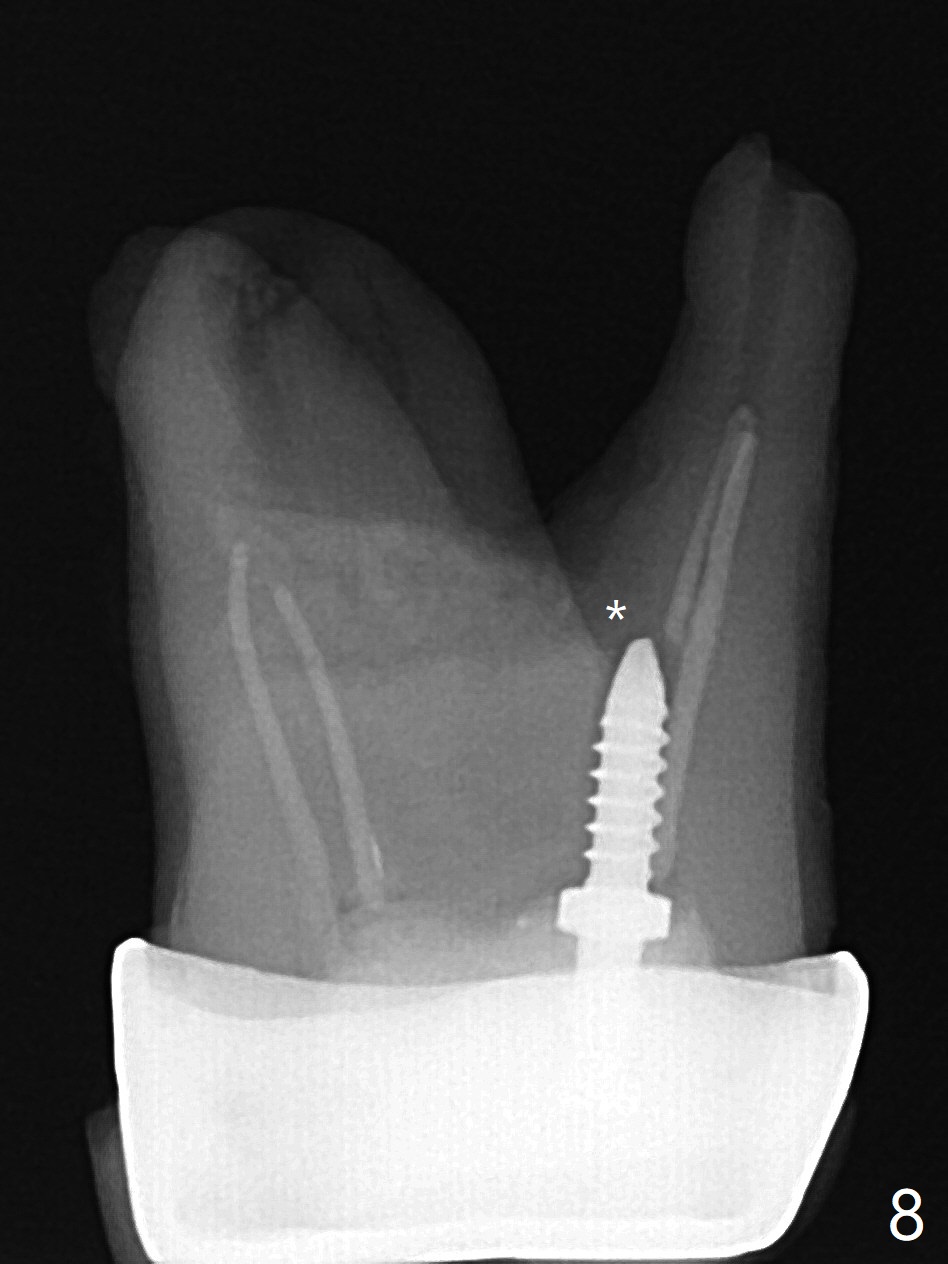

A 29-year-old man has pain in the upper left quadrant. It appears that the tooth #14 has endo and post failure with palatal fistula (Fig.1,2). The septum is almost non-existent; the palatal wall is low, while the sinus floor is present. Sticky bone is placed first against the defective palatal wall and presumably pushed as high as to the sinus floor (Fig.3-5). PRF plug/membrane and 6-month membrane are used to close the socket with 4-0 Chromic gut suture apparently securely, followed by periodontal dressing. Examination of the extracted tooth shows granulation tissue between the roots (Fig.6 *). Underneath the granulation tissue is cement-like material (Fig.7 C). Distal-to-mesial X-ray examination shows possible furcation perforation (Fig.8 *), while mesial-to-distal one the cement-like material in the furca and pulpal chamber as well as MB2 (Fig.9 >). The patient returns 8 days postop, reporting pain reduction, but wants to have #16 extracted. The periodontal dressing is loose, but stuck with 2 sutures underneath. When the dressing is removed, the wound looks normal (Fig.10). In fact the dressing is re-applied. The 6-month membrane has lost 1 month postop. The majority of the socket heals except the palatal (Fig.11 *), as related to the existing palatal fistula/defect (^). Orthodontics is being considered. If the buccal plate collapses 4.5 months post extraction, socket shield should have been done. In fact the buccal plate is robotic, while the bone density is low palatal in CT (Fig.12).